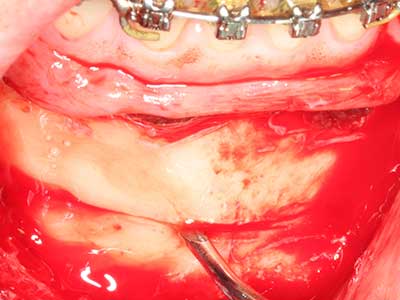

Bone tissue is not simply a mineral structure but also contains a substantial proportion of collagen fibres. This means it not only has good compressive strength but also a degree of flexibility, which can be taken advantage of when performing bone augmentations. In the classical expansion procedure using bone splitting, the atrophied alveolar ridge is split longitudinally and carefully expanded after reaching an adequate osteotomy depth (Fig. 13-16), ideally without substantial removal of the periosteum (Brugnami, Caiazzo et al. 2014, Stricker, Fleiner et al. 2014). Screw and plate systems with increasing expansion distance have proven effective in separating the two bone lamellae while remaining below the fracture threshold. In general, residual bone widths of at least 3–4 mm are required (Chiapasco, Zaniboni et al. 2006) to guarantee adequate flexibility and sufficient bone coverage of the future implants. If necessary, a vertical relief osteotomy on one or both sides can improve flexibility. A combination with additional augmentation techniques, particularly on the buccal side, has been described as an alternative to the classical technique.